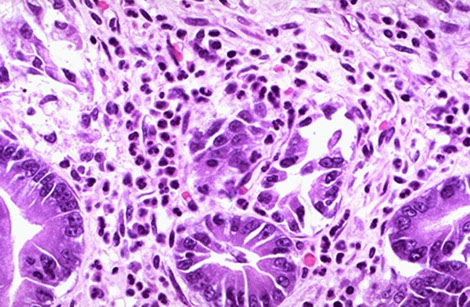

Adenocarcinoma (AC)

MCC stomach cancer (90-95%), M>F, higher risk in Eastern countries, South America, AMAG also puts at risk; is occurring more in gastric cardia

- Can be divided into intestinal (bulky) and diffuse (more often have signet ring cells) types

Intestinal type AC assoc c H pylori infx

-- Lauren classification found intestinal type-tumors have better survival than diffuse type

Hereditary diffuse gastric carcinoma assoc c mutation in E-cadherin or alteration of its gene expression

- has AD pattern of inheritance

Early aggressive local spread and lymph node/ liver mets

- asymptomatic until late; mets usually found at dx

Assoc w/ nitrosamines (smoked foods), achlorhydria, chronic gastritis (H pylori), type A blood

- gastric adenomas and dysplasia are precursors

Signet ring cells and acanthosis nigricans common features.

Linitis plastica ("leather bottle") may occur when diffusely infiltrative

Tumor may also be: ulcerating, polypoid, or superficial spreading

Virchow node: mets to L. supraclavicular node

Krukenberg's tumor: bilateral mets to ovaries. Abundant mucus, Signet ring cells

Sister Mary Joseph nodule: subcutaneous periumbilical mets

Irish node - enlarged left axillary lymph node

Leser-Trelat syndrome: sudden dermatologic onset of seborrheic keratosis (look for underlying gastric malignancy)

Micro: intestinal type tumors are large masses that form c intestinal metaplasia in background

- diffuse type seem to arise de novo in normal mucosa background, can be sneaky and have signet rings and look like macrophages from lower power

- may appear hepatoid (poor px; +SALL4), clear cell, squamoid, micropapillary

- lymphoepithelial-like AC is lacy and can be EBV+

IHC: (+) HER2 regularly suggested (from ToGA trial; HER2 IHC is superior to FISH), CDX2, CK7, CK20 (while keratins can be helpful, should not be used on all ulcers bc can highlight scurry lookin single cell pattern in regenerative tissue); PAS/AB reveals abnormally colored cells and has strange effect on mucin;

- negative CD44, EBV, E-cadherin (in hereditary AC)

Like breast cancers, ~20% of gastric cancers and 30% of gastroesophageal junction cancers overexpress HER2

- unlike breast cancer Her2 overexpression by either FISH or IHC is evidence of likely response

Labs: inc CEA in 45-50%; CA19-9 in 20%

- may consider HER2 by FISH if IHC is equivocal

Genes: ~1/2 sporadic diffuse are hereditary, assoc c CDH1 gene (encodes E-cadherin); has 7/10 penetrance; esp get signet ring AC and also assoc c lobular ca of the breast

- prophylactic gastrectomy may be offered to CDH1 gene carriers; CDH1 mutations assoc c gastric signet ring ca and lobular carcinoma of the breast

- sporadic intestinal type assoc c Wnt pathway mutations (such ass loss-of-function of APC tumor suppressor gene and gain-of-function of B-catenin

DDx: chemical gastropathy, crushed oxyntic mucosa

Tx: Distal 1/3: subtotal gastrectomy

- proximal 2/3 or infiltrative lesions: Total gastrectomy w/ adjuvant chemo and rads

- trastuzumab in HER2+ cases

Px: depth of invasion and extent of nodal and distant mets are most impartant px factors

- 1/2 of pts die of dz; AC found outside cardia has better px vs gastric cardia AC

- stage assoc c survival (Lauren classification)

AJCC staging Gastric cancer

In situ signet ring cells in gastrectomy for hereditary diffuse gastric cancer, mutation in CDH1

Pitfall -- crushed mucosa with prominent mucus neck cells note the sloughed

single cells are seen in gland lumina oil immersion (bad idea)

Hereditary Diffuse Gastric Cancer (HDGC)

major cause is germline mutations in CDH1, which encodes e-cadherin; thus pts c HDGC at risk for lobular breasst ca and diffuse signet ring cell ca

- prophylactic gastrectomy is the only way to prevent gastric ca in pts c CDH1 mutation